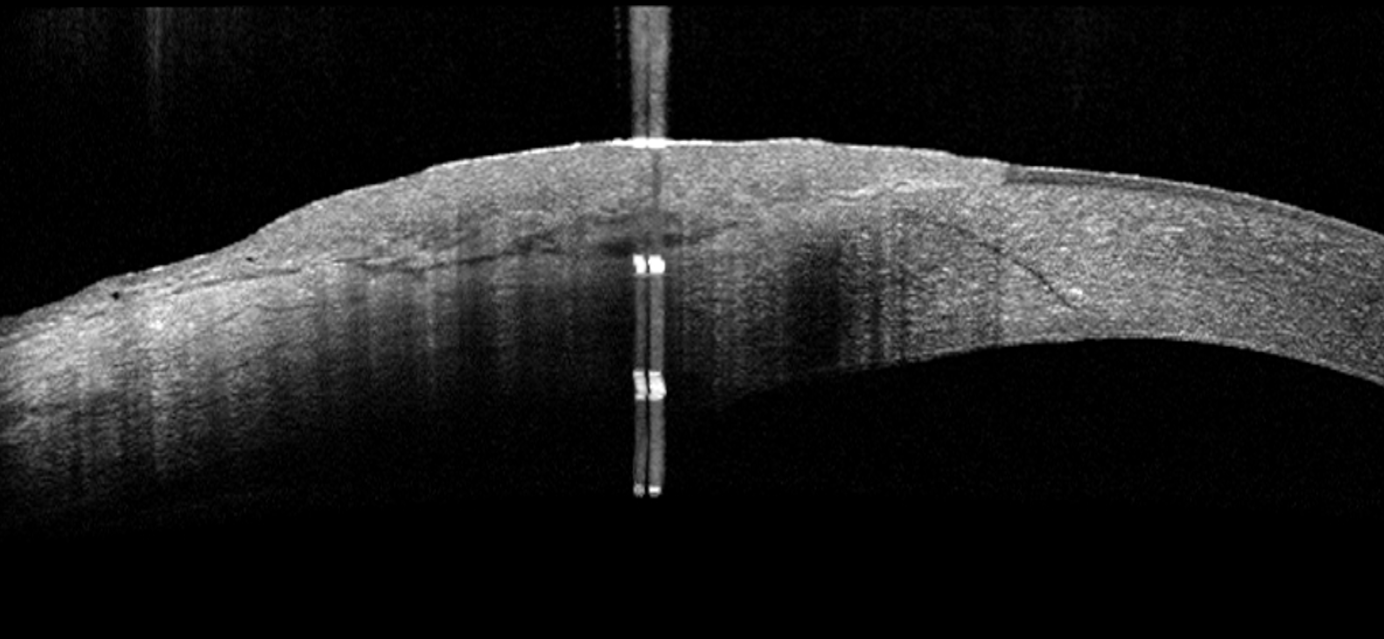

Using AI to Diagnose Tumors of the Ocular Surface

High-resolution anterior segment optical coherence tomography has enabled the non-invasive diagnosis of cancers of the surface of the eye. Our team is working on methods to automate the imaging and diagnosis of ocular surface tumors using AI, as well as attempting to identify novel imaging biomarkers with diagnostic and prognostic value.